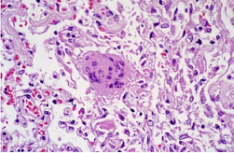

病理標(biāo)本的一種,制作時(shí)將部分有病變的組織或臟器經(jīng)過(guò)各種化學(xué)品和埋藏法的處理,使之固定硬化,在切片機(jī)上切成薄片,粘附在玻片上,染以各種顏色,供在顯微鏡下檢查,以觀察病理變化,作出病理診斷,為臨床診斷和治療提供幫助。

常用的染色方法是蘇木素-伊紅(Hematoxylin-Eosin)染色法,簡(jiǎn)稱(chēng)H.E染色法。這種方法對(duì)任何固定液固定的組織和應(yīng)用各種包埋法的切片均可使用。蘇木素是一種堿性染料,可使組織中的嗜堿性物質(zhì)染成藍(lán)色,如細(xì)胞核中的染色質(zhì)等;伊紅是一種酸性染料,可使組織中的嗜酸性物質(zhì)染成紅色,如多數(shù)細(xì)胞的胞質(zhì)、核仁等在H.E染色的切片中均呈紅色。